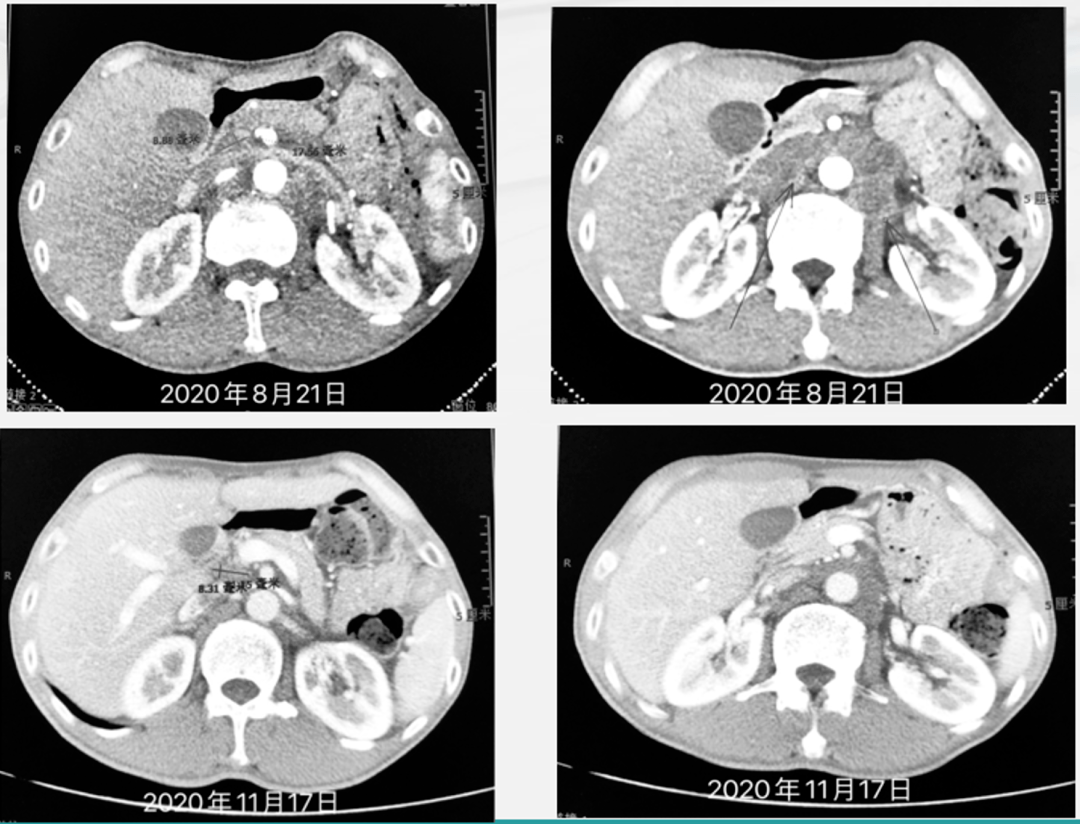

实例鉴证,携爱而行|局部晚期胃癌患者呋喹替尼联合紫杉醇转化治疗后

免疫联合化疗助力晚期胃癌患者实现r0切除